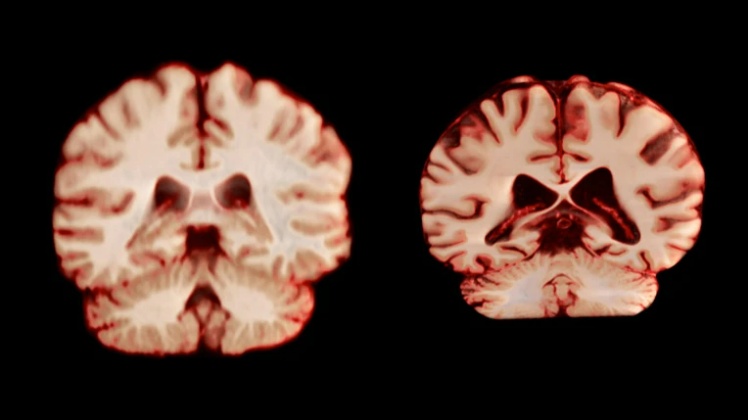

健康的大脑(左)和受阿尔茨海默病影响的大脑。图源:Nature,Anatomical Travelogue/SPL

更关键的是,与AD密切相关的海马体体积,在老年男女中的衰退速度并没有差异。这意味着,从核心脑区的衰老情况来看,女性并不比男性更“易感”。